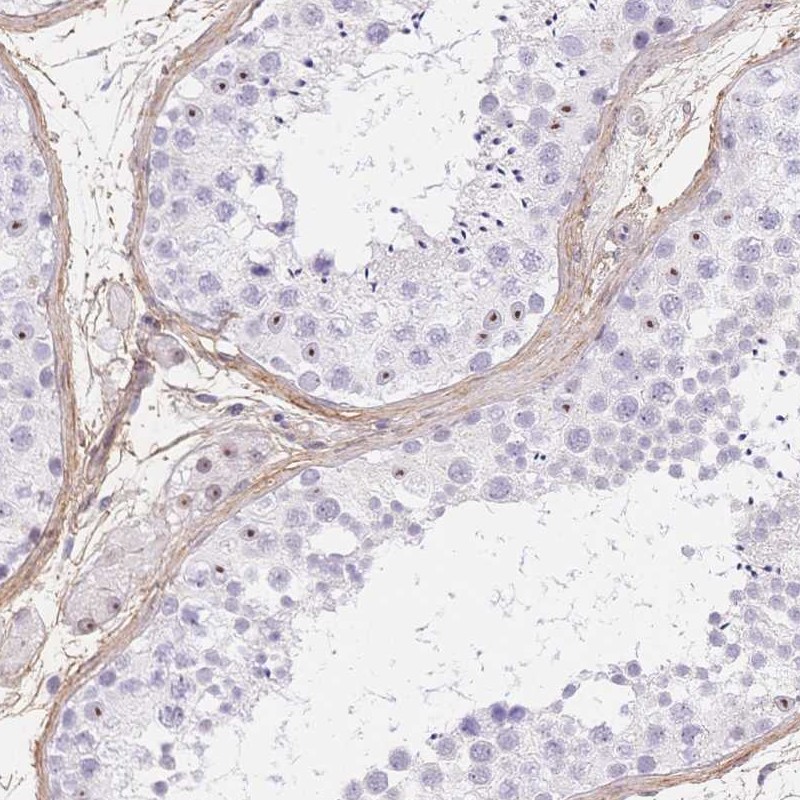

Immunohistochemical staining of human testis shows nuclear positivity in cells in seminiferous ducts and Leydig cells.